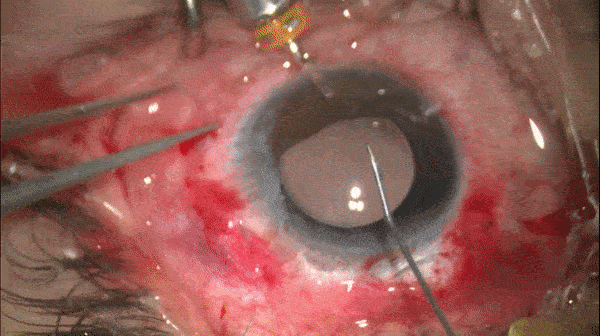

调整缝线张力以居中IOL

开睑器怎么用术说睛彩 | 金海鹰教授:使用8-0缝线的无巩膜瓣人工晶体固定手术_https://www.jmylbn.com_新闻资讯_第8张